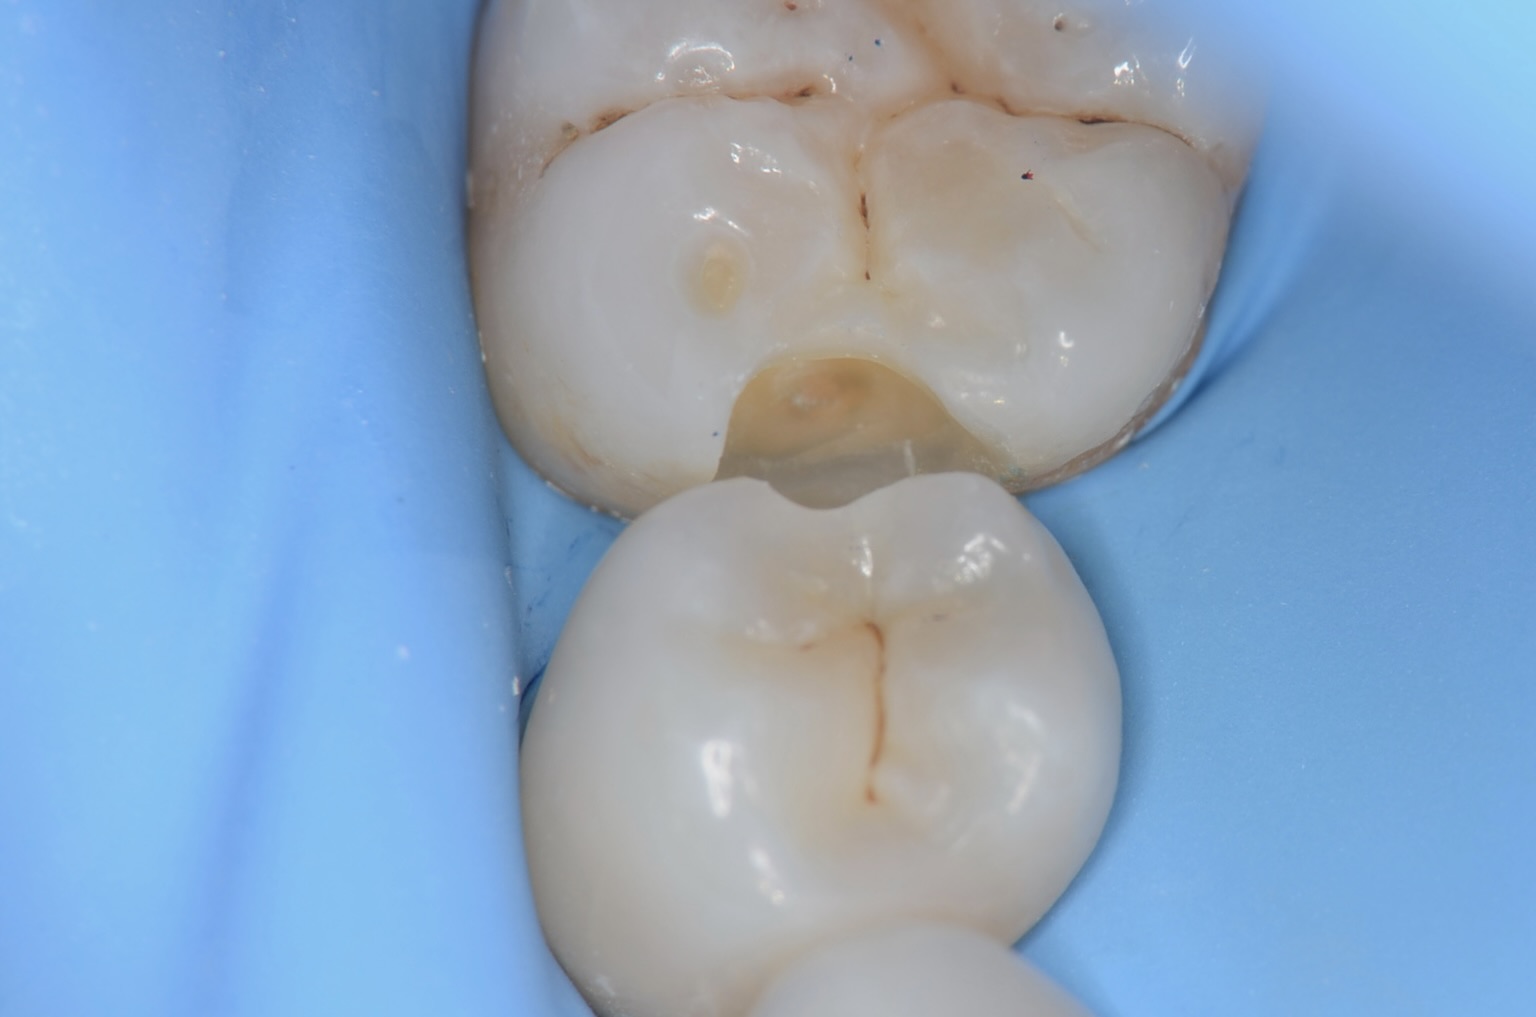

5番遠心虫歯

6番の近心から虫歯を除去し、その空間から5番遠心の辺縁隆線をできるだけ、削らないようにします。 -

5番遠心虫歯除去

6番近心

咬合面観